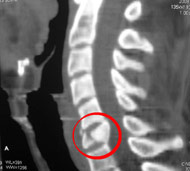

- Комп'ютерну томографію (КТ). КТ може надати краще зображення патології, видимої на рентгенівських знімках. Цей вид обстеження використовує комп'ютер, щоб відтворити серію зображень поперечного перерізу, які можуть виявити проблеми, пов'язані з кістками, дисками і інші.

- Мієлографію. Мієлографія дозволяє лікарю візуалізувати нерви хребта більш чітко. Після введення контрастної речовини в хребетний канал на рентгенівських знімках або КТ хребців можна виявити грижі міжхребцевого диска або пухлини. Цей тест застосовується, коли проведення МРТ є неможливим або коли мієлографія може надати важливу додаткову інформацію, яку неможливо отримати при проведенні інших досліджень.